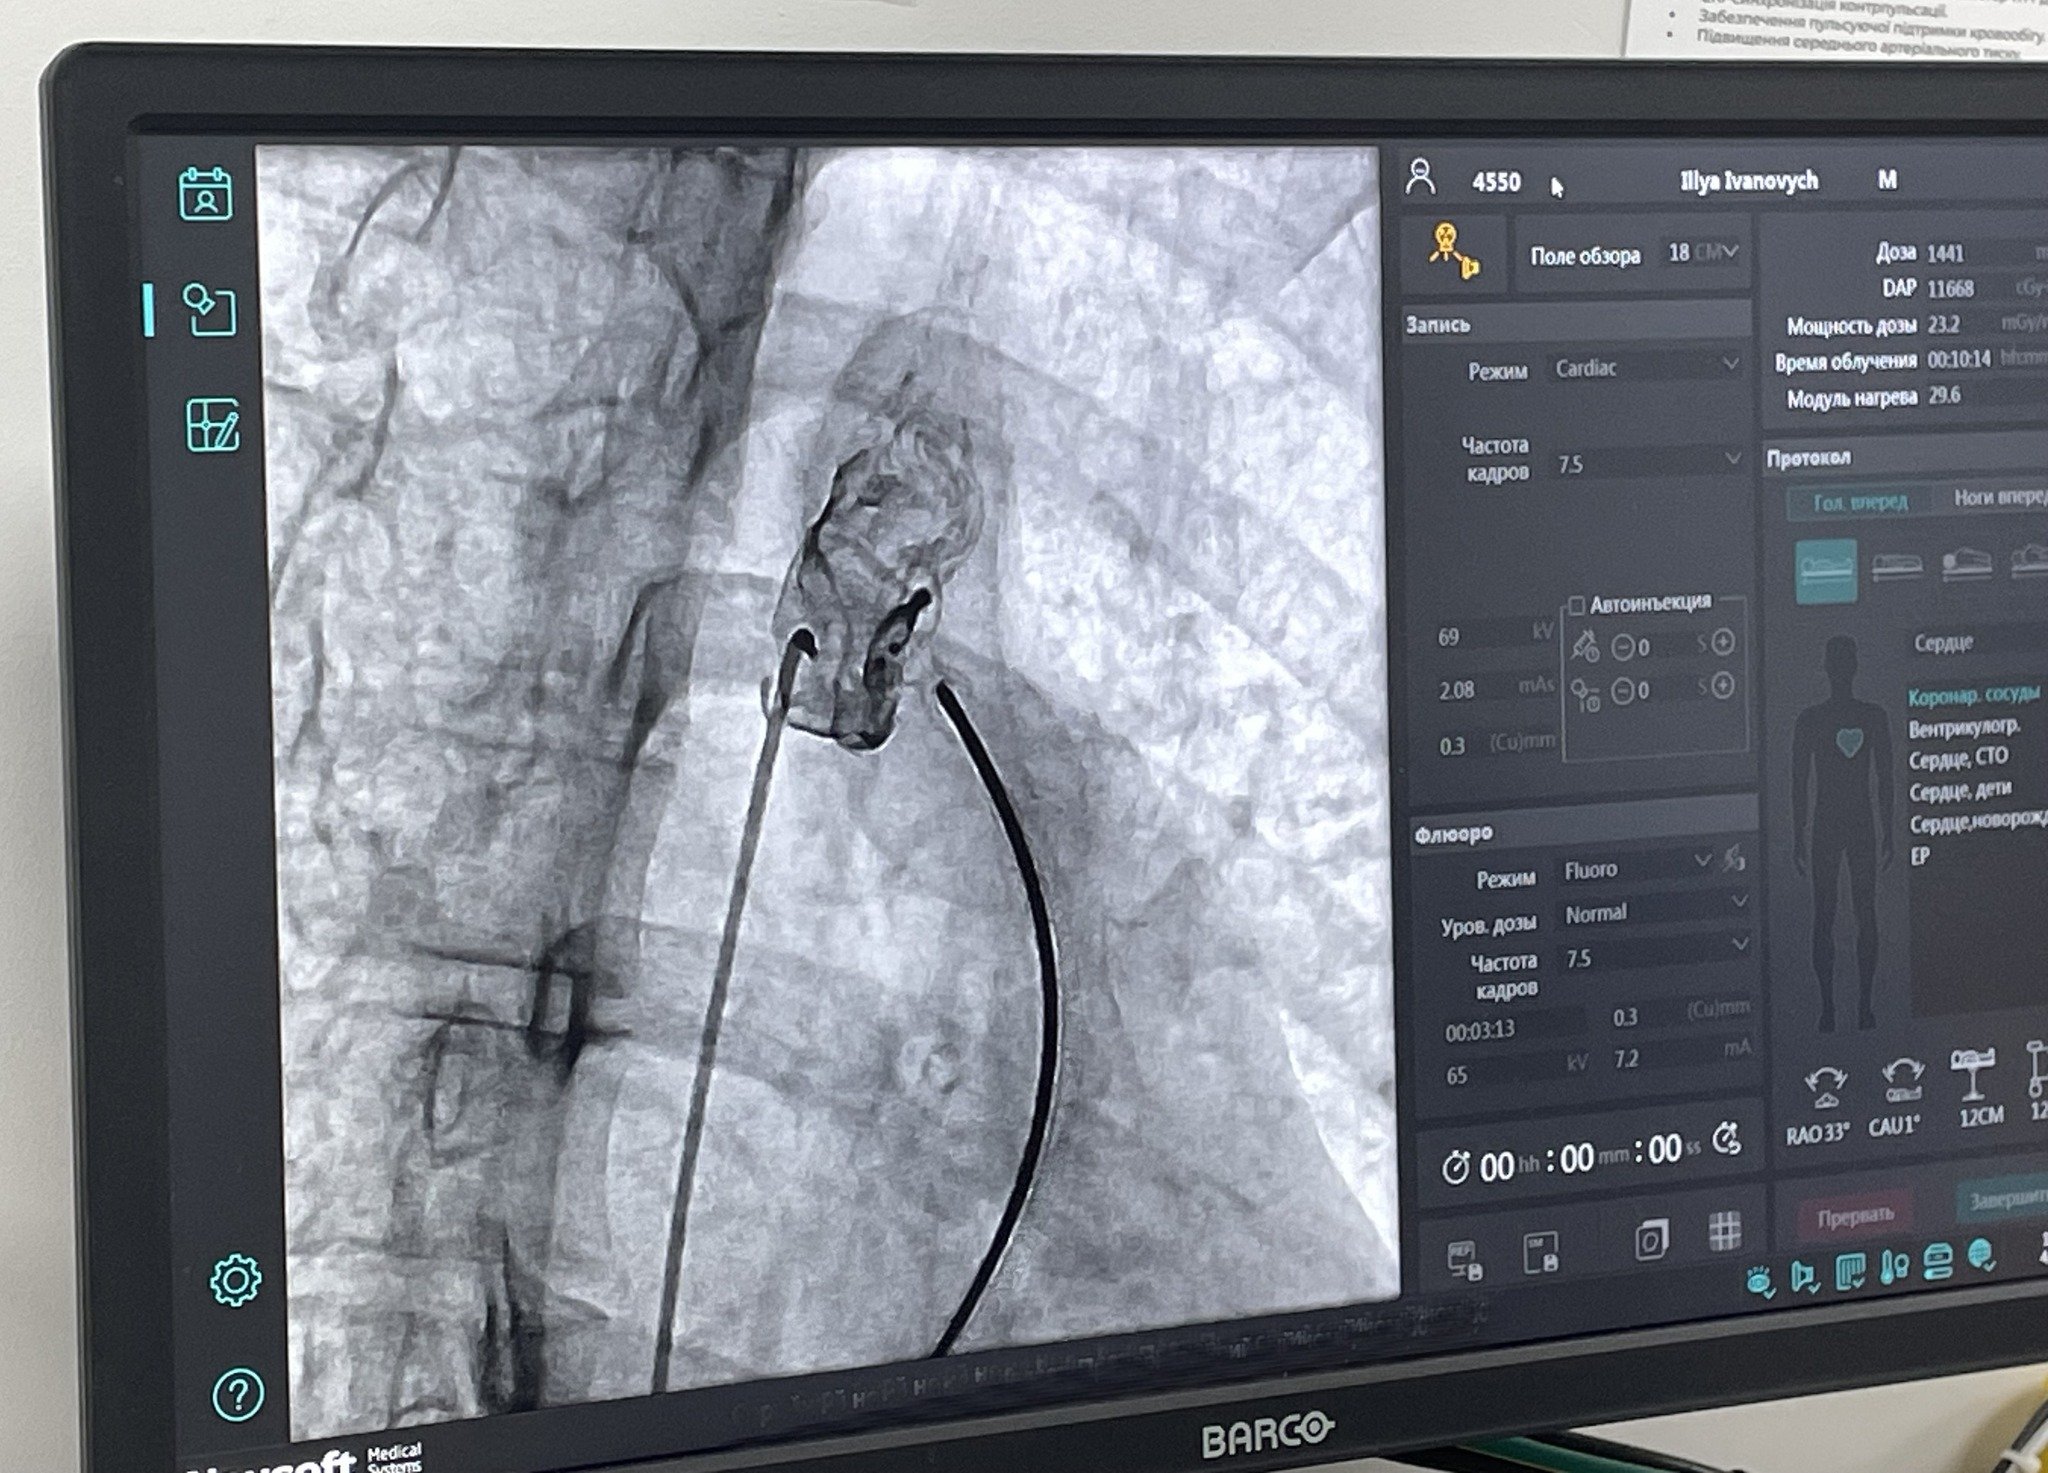

Операція пройшла успішно. Корекцію вади серця виконали ендоваскулярно, протоку закрили за допомогою оклюдера (штучний імплант отримано в рамках програми лікування хворих із серцево-судинними захворюваннями МОЗ України).